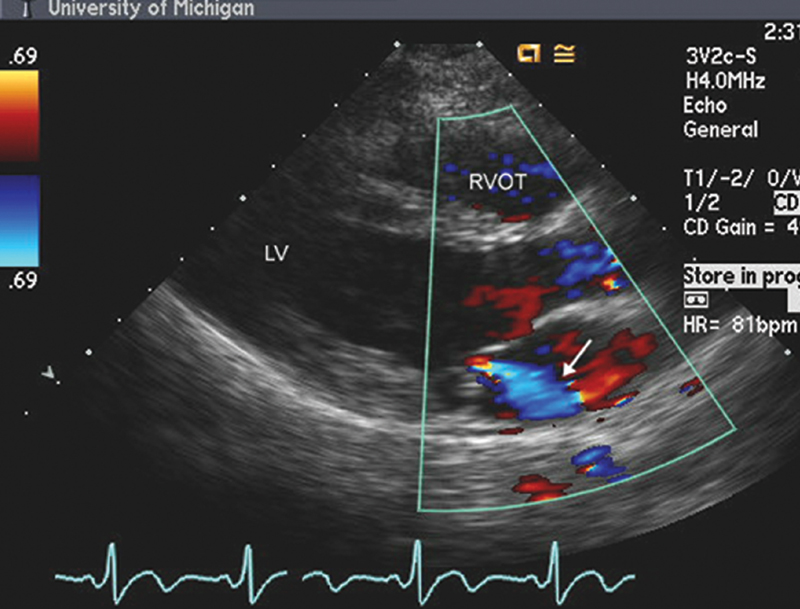

فحوصات تشخيصية لبعض امراض القلب والشرايين التاجية